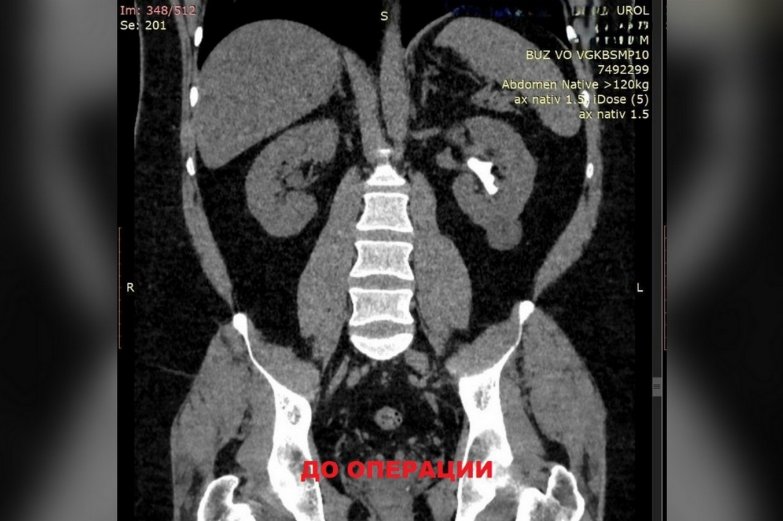

Врачи Воронежской городской клинической больницы скорой медицинской помощи №10 (БСПМ №10) выполнили сложную операцию по удалению камня в почках. В больницу обратился 38-летний воронежец с жалобами на боль в левой части поясницы. Специалисты выяснили, что у мужчины большую часть чашечно-лоханочной системы левой почки занимает камень размером 27 на 39 мм. Отягощающим фактором была избыточная масса тела пациента – он весил 142 кг. Врачи выполнили тяжелую операцию без открытого разреза. Через пять дней пациента выписали домой. Об этом сообщили в пресс-службе регионального министерства здравоохранения в четверг, 4 сентября.